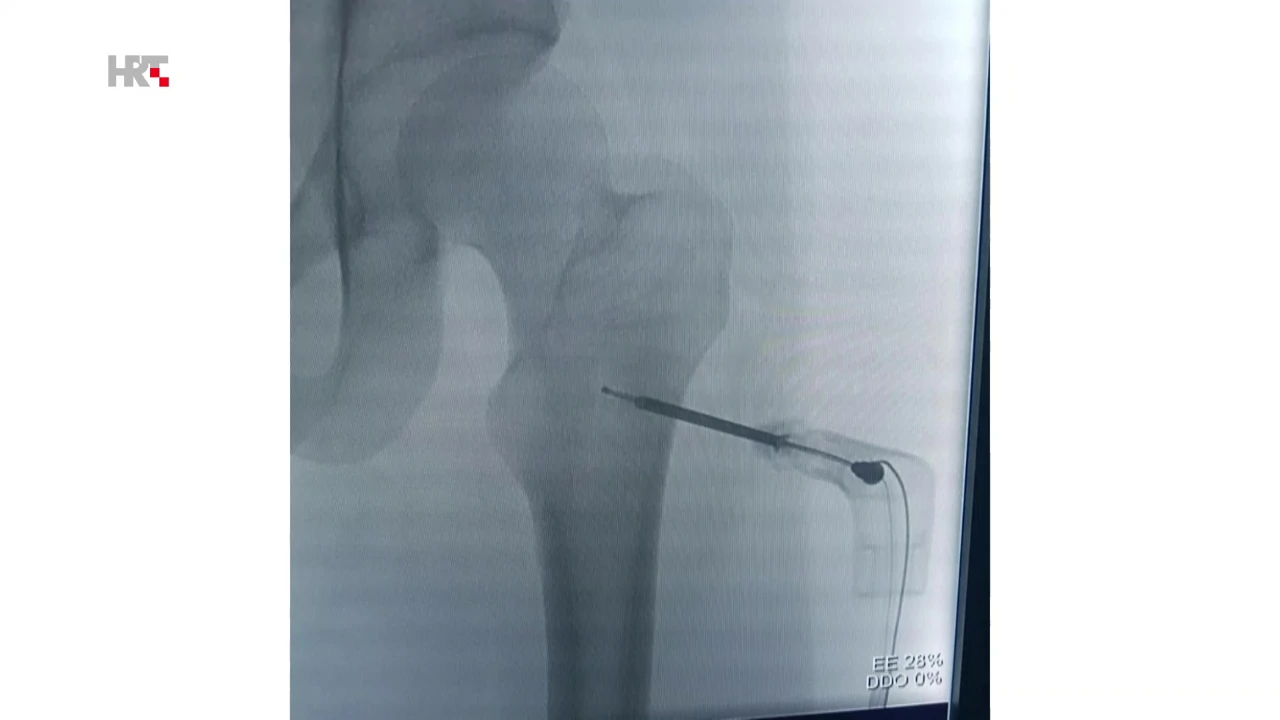

- Osmislio se način kako se precizno, pod kontrolom najčešće CT-a ili ultrazvuka, može iglicom ući u tumor. To može biti u različitim organima – bubregu, jetri, u kostima, čak i u plućima. Nakon što se ta iglica precizno pozicionira u tumor, toplinskom se energijom, laički rečeno - tumor sprži, uništi ga se. Ono što je važno, on ostaje unutra međutim ostaje kao mrtvo tkivo koje više ne predstavlja opasnost, kaže Luka Novosel, spec. radiologije iz KBC-a 'Sestre milosrdnice'.

Primjena ovakvih inovativnih metoda, osim edukacije liječnika, zahtijeva i korištenje suvremenih medicinskih uređaja i alata. Postupak se provodi iglom koja na vrhu, u zadnjih 2 cm - stvara različite vrste energije. U zadnje vrijeme koristimo mikrovalnu energiju kojom se potiče molekule vode u tumoru da se kreću, objašnjava Novosel. Tim trenjem stvara se toplina koja doseže i do 100 stupnjeva Celzijevih. Ona uništava tkivo u krugu od 3-5 cm.